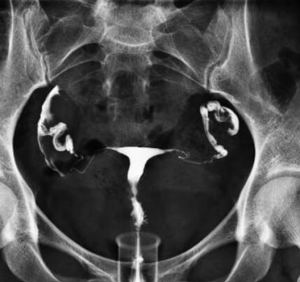

Hystérosalpingographie

Permet de vérifier la perméabilité tubaire avec l’aide de rayons X après instillation dans la cavité utérine de produit de contraste iodé

Se réalise entre le 7é et le 14é jour du cycle.